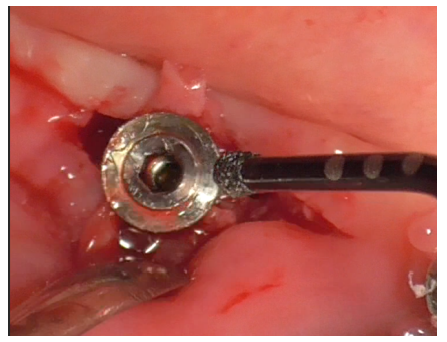

After thorough rinsing, EDTA gel was applied to the site (Figure 27) and activated for 1 minute using the bell-shaped insert (Figure 28).

Figure 27

Figure 28

The decontaminated implant with exposed threads is revealed (Figure 29).

Figure 29